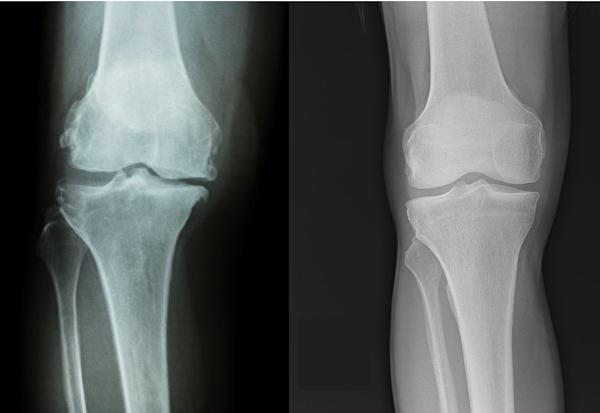

膝盖是由股骨(大腿骨)、髌骨(膝盖骨)、胫骨(小腿骨)三者组成的,骨头跟骨头之间又有一层软骨作为缓冲、降低摩擦之用。膝盖退化性关节炎的最大特点,就是这层软骨的流失(注1)。

软骨磨损的膝关节(左)和正常的膝关节(右)。

上面右图是正常的膝关节,可以看到骨头与骨头之间有充足的空间,这层空间由软骨所占据。而左图的膝关节内侧的空间明显变窄了,这意味着软骨的厚度降低(注2)。